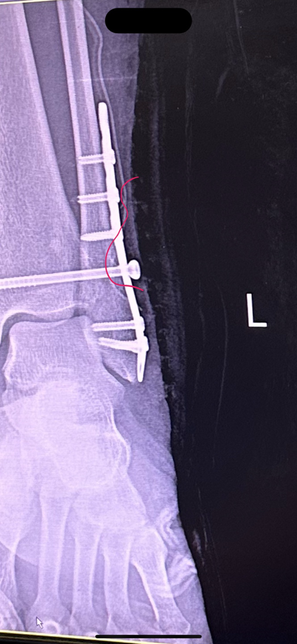

- 의료법률노련한참밀드리138골절 수술 후 체내 쇳조각이 살을 뚫고 나옴12/11 발목 골절 수술(심 박는) 받았습니다 수술 진행 후 엑스레이도 찍고 무사히 잘끝났다는 말에 안심하고 시간을 보낼 수 있었습니다 그리고 일주일간 입원 후 퇴원한 뒤 수술한지 2주가 지난 시점 지금까지 감고 있던 붕대를 풀고 집으로 돌아간 뒤 확인해보니 저렇게 낚시바늘같은것이 살을 뚫고 나와있었습니다당장 주말과 크리스마스연휴라 내원을 하지 못하고 몇일이 지나 내원을 했더니 이런 쇳조각이 몸안에서부터 살을 뚫고 나왔던겁니다자초지종을 물어보니 심을 박는 과정에서 판과 심의 마찰때문에 해당 쇳조각이 생성이 되었다고 하더라구요 백번 양보해서 쇳조각이 생성될 수도 있지만 이대로 봉합했다는 사실이 충격이었구요 설마 알면서 그랬다고는 상상하기싫고 몰랐다는것도 상상하기 힘듭니다 해당 엑스레이를 그당시에는 설명안하고 제가 내원했을 때 설명하시더라구요 "여기선 잘 안보여" 라고 하는데 일반인인 제가 여기있다고 말씀드렸습니다. 심지어 다른각도에서는 더 잘보이구요. 그래놓고 허겁지겁 다음 예약 잡자 말을 돌리시더라구요마지막에는 진료비까지 내라 하시던데 해당 내용 제가 보상받을 수 있을까요1명의 전문가가 답변했어요